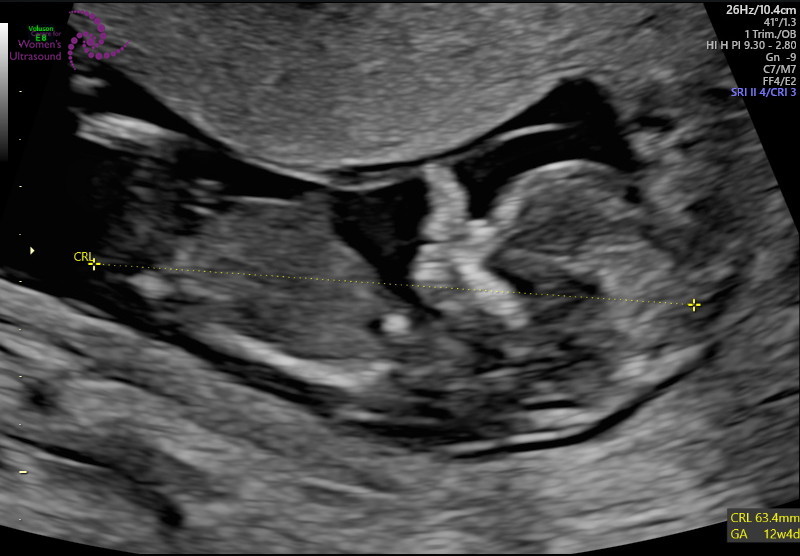

12주 정밀 초음파

젤리곰 탱이를 볼 수 있어요

아기 사이즈 및 기형아 체크

손, 발 길이 등등

자세하게 하나하나 체크하면서

초음파를 보기 때문에 약 40분가량 걸렸어요

양수량이 적당한지

아이가 잘 있는지 등등 체크하는데

화면으로 보는데 너무 신기하더라고요

저렇게 작은데 손, 발이 다 있다니...

울트라사운드라 아이가 초음파 하는데

움직이는 모습도 볼 수 있었어요